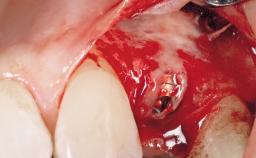

A 30-year-old female patient had lost tooth 21 and was referred to our clinic for consultation and treatment. Due to advanced apical infection, tooth 21 had been extracted two months earlier at another clinic and an acrylic-resin tooth had been bonded to the adjacent teeth. The patient desired implant treatment to avoid any damage to the adjacent natural teeth. While the patient had no history of any systemic disorder, she was a heavy smoker and exhibited medium to advanced periodontitis in the entire jaw. After the initial treatment to achieve a pocket probing depth of less than 4 mm and no bleeding on probing, a decrease in the height of the papillae mesial and distal to the extraction site and overall gingival recession were observed.

| Type of Implants | One-Piece|Reduced-Diameter |

| Placement Protocol | Early or late implant placement |